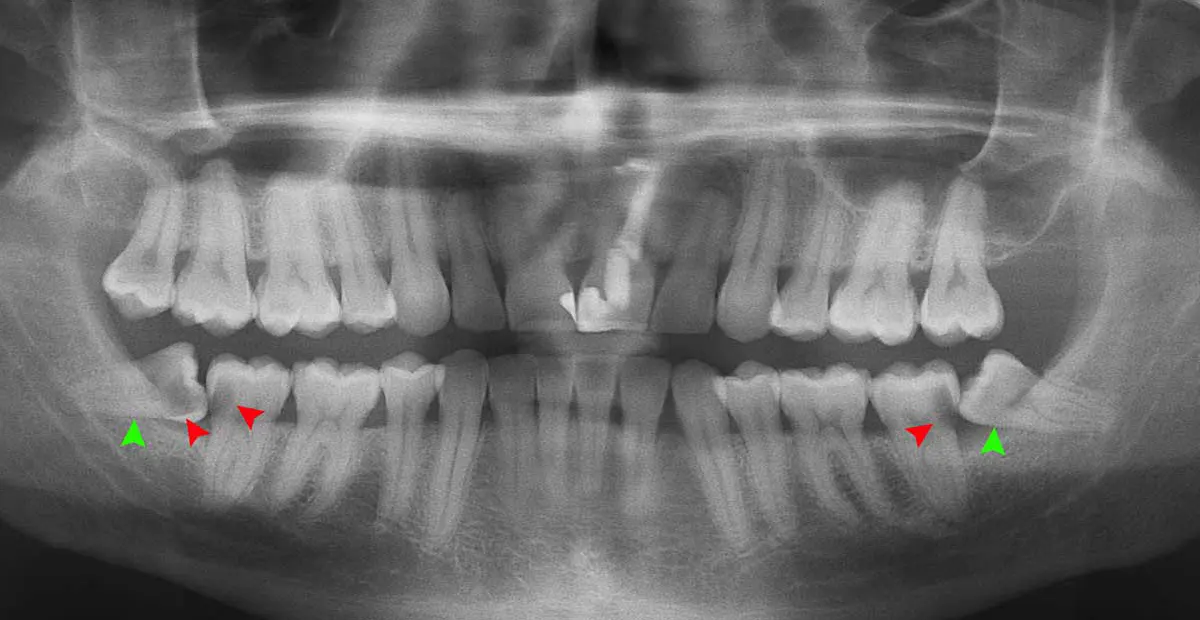

اشعه ایکس و تصویربرداری

اشعه ایکس و تکنیکهای تصویربرداری نقش کلیدی در تشخیص دندانهای نهفته و نیمه نهفته ایفا میکنند. این تکنیکها به دندانپزشک اجازه میدهند تا تصاویر دقیقی از ساختار داخلی دهان، شامل استخوانها و دندانها، به دست آورد. با استفاده از این تصاویر، دندانپزشک میتواند موقعیت دقیق دندان نهفته، جهتگیری آن و نزدیکی آن به دندانهای دیگر را ببیند.

این تصاویر همچنین به دندانپزشک کمک میکنند تا ببیند آیا دندان نهفته به دندانهای مجاور فشار میآورد یا باعث ایجاد مشکلات دیگری مانند کیست یا تومور شده است یا خیر. با اطلاعات به دست آمده از اشعه ایکس و تصویربرداری، دندانپزشک میتواند تصمیمات درمانی دقیقتری بگیرد و برنامهریزی مناسبی برای استخراج یا درمان دندان نهفته انجام دهد. این روشها بسیار مهم هستند زیرا بدون آنها، تشخیص دقیق و کامل دندانهای نهفته و نیمه نهفته ممکن نیست.